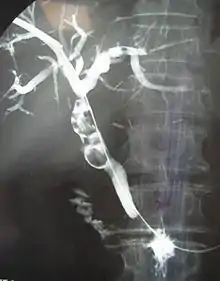

Pancreatitis

Pyloric Ulcers